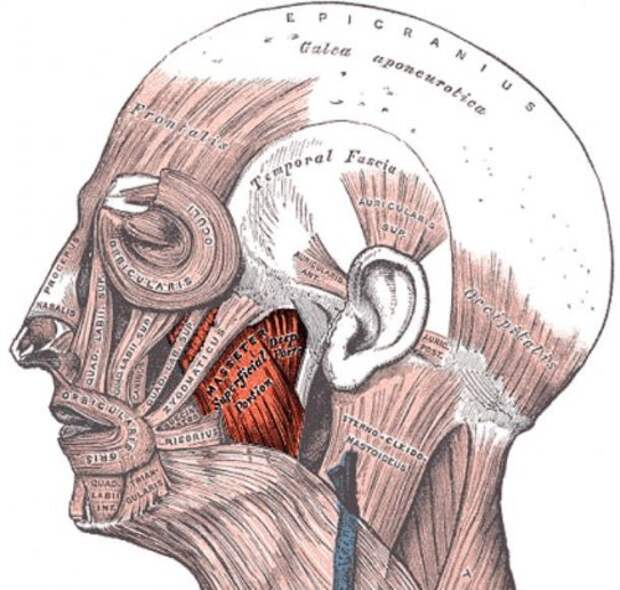

15. Учитывая вес и силу, самыми сильными мышцами в нашем теле являются жевательные мышцы. Эти мощные мышцы ответственны за процесс жевания (привет от Кэпа).

9. Существует распространённый миф о том, что когда человек хмурится, работают 43 мышцы, а когда улыбается — всего 17. Каждый раз, когда человек улыбается или хмурится, в этом участвует разное количество мышц в зависимости от каждого конкретного человека. Никто не может с абсолютной точностью сказать, сколько мышц человек использует, когда улыбается.